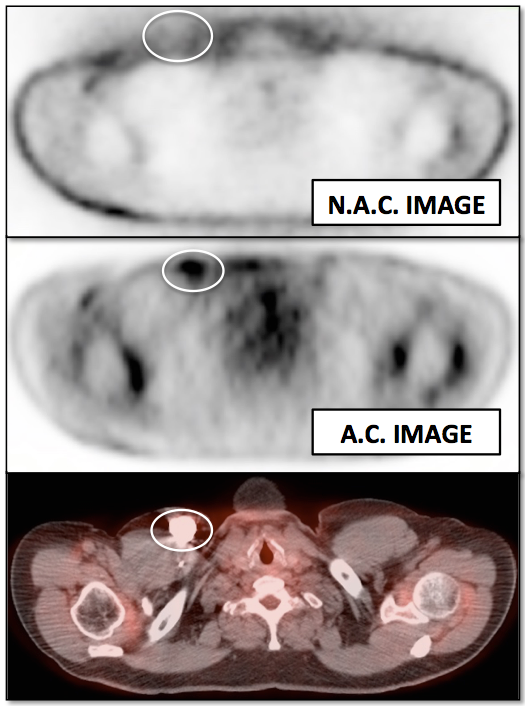

Value of Non-Attenuation Corrected (NAC) Images

Resolving Attenuation Correction Artifacts:

The CT images obtained during an exam are not only used for “anatomic” interpretation. They are also used for “attenuation correction” (AC) of the PET images, generating the much more useful AC PET images used for interpretation.

Unfortunately, attenuation correction of PET images can result in falsely elevated metabolic activity in regions of high CT density (e.g. metallic devices, oral contrast, calcification).

In such cases, these areas must be reviewed on the NAC (non-attenuation correction) images. If these regions are not also hypermetabolic on the NAC images, then their apparent increased FDG-uptake on the AC images is artefactual.

This phenomenon is almost exclusively seen with older PET/CT scanners, as most modern scanners utilize newer algorithms that do not “over-correct” in these areas of increased density.